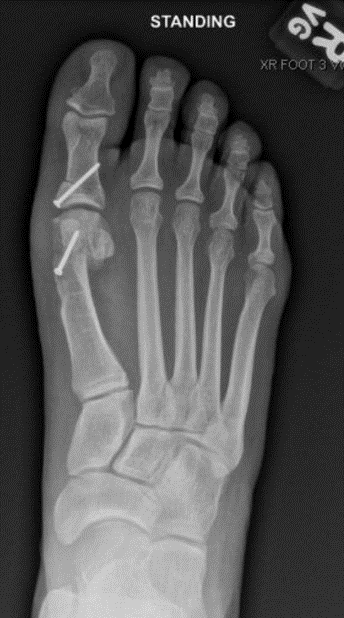

Hallux valgus-bunion deformity

Figure 1: Hallux valgus (bunion deformity)

Bunions

A bunion, also known as hallux valgus, is a bony prominence at the base of the big toe, which often results in pain, redness, and rubbing in footwear. The 1st metatarsal bone abnormally angles outward towards the other foot from its joint in the midfoot. A bunion can change the shape of your foot, make it difficult for you to find shoes that fit correctly, and worsen the symptoms if left untreated.

The diagnosis of a bunion includes taking a medical history and performing a physical examination to assess the extent of misalignment and damage to the soft tissues. Weight-bearing X-rays are taken while standing to assess the severity of the bunion and deformity of the toe joints.